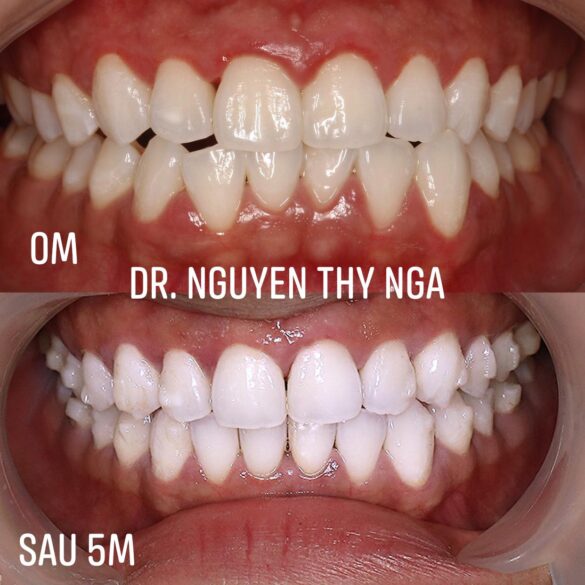

Chia sẻ một số case chuyên môn

#khớpcắnhở #openbite Dr. Thy Nga Nguyen